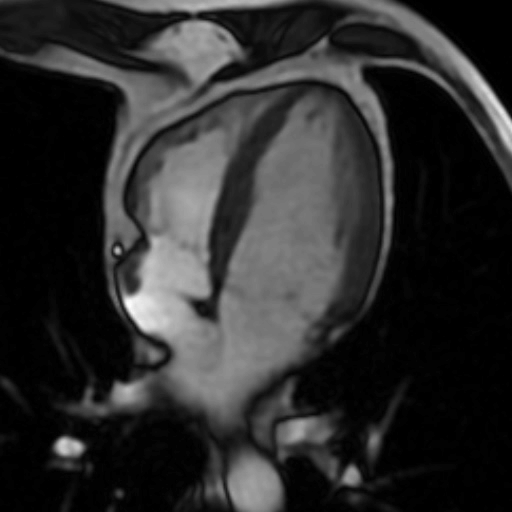

L’ IRM permet d'obtenir des vues en deux ou en trois dimensions d'une très haute précision (moins d’un millimètre).

La précision de l’IRM en quelques images: